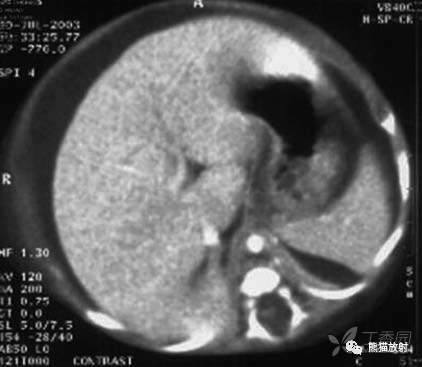

内脏结核

VISCERAL TUBERCULOSIS

肝和脾实质内弥漫性针尖状低密度灶伴腹膜炎、腹水

肝内多发低密度小结节

胰腺头、体部近段多发低密度小结节,胰头点状钙化